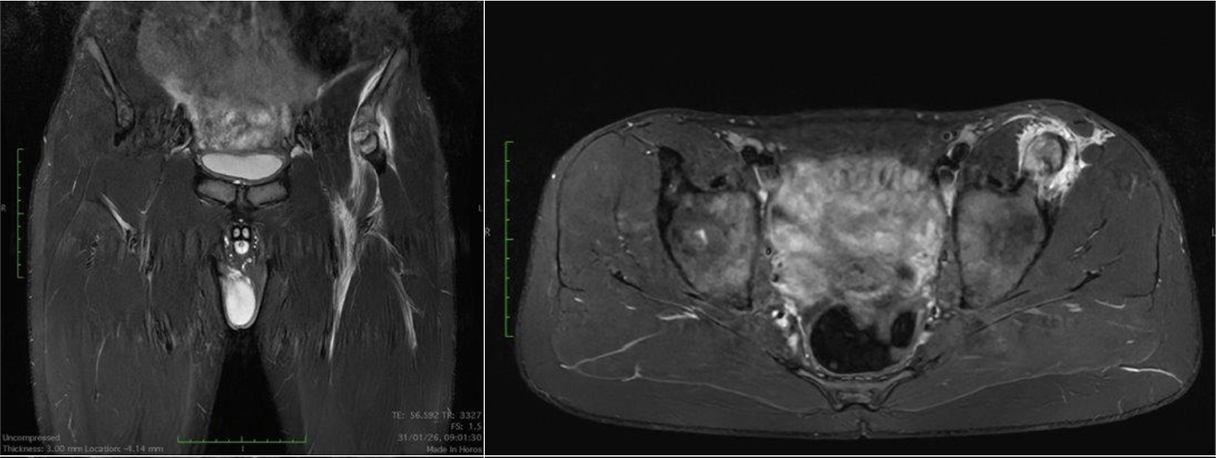

Casi clinici

Scopri come le tecnologie di imaging più innovative di GE HealthCare hanno giocato un ruolo chiave nella diagnosi di condizioni cardiache complesse.